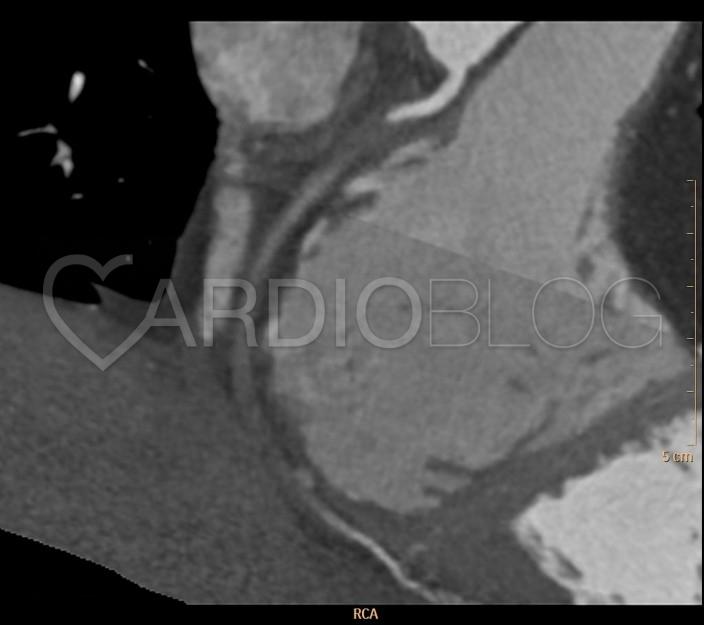

A domináns jobb coronaria azonban a proximalis szakaszán segmentalisan occludaltnak bizonyult, a distalis érszakasz kontraszttal csak igen halványan telődött.

A panaszok hátterében tehát egy akutan zajló coronaria syndroma állt, a coronarographia elvégzése így már nem lehetett kérdéses. A beteg EKG-ján a CT vizsgálat után többszöri nsVT (nem tartós kamrai tachycardia) volt látható, amelyet rövid keringésmegingás kísért, ezért a katéteres laborba már szedálva, intubálva érkezett.

A sürgős coronarographia közben az EKG-n már egyértelműen inferior STEMI képe rajzolódott ki. A koszorúérfestés alátámasztotta a CT-n látottakat, az occludalt jobb coronarian intervenció történt BMS stent beültetésével. A beteg ezt követően stabil állapotban került az intenzív osztályra, ahol az ismételt laborvizsgálat már emelkedett nekroenzimeket mért. Néhány napos megfigyelést követően betegünk panaszmentesen távozott a kórházból.